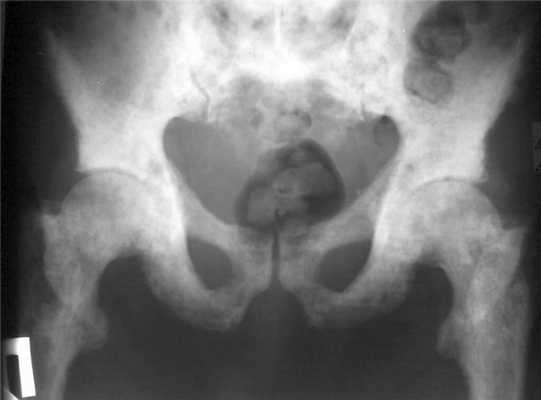

- Рентген. Ретроградная цистография считается «золотым стандартом» диагностики этого вида травм. Разрывы органа проявляются затеками рентгеноконтрастного вещества в пузырно-прямокишечную ямку, околопузырную клетчатку, область крыльев подвздошной кости, полость брюшины.

(Слева) КТ с контрастированием, аксиальный срез: диастаз лобкового симфиза и скопление жидкости в мягких тканях спереди; зачастую затруднительно определить, является ли это скопление мочой или гематомой, или и тем, и другим.

(Справа) Контрольная цистография, передняя проекция: у этого же пациента определяется экстравазация контраста из мочевого пузыря в ткани внебрюшинного пространства, окружающие мочевой пузырь, а также вдоль верхней трети левого берда и мошонки. Небольшое количество контраста определяется в мочевом пузыре. (Слева) КТ с контрастированием, выполненная для оценки первичной травмы, аксиальный срез: околопузырное скопление жидкости. Дифференциальный диагноз включает скопление мочи или крови. Небольшое кровотечение заметно в подкожной клетчатке спереди и в околопрямокишечном пространстве.

(Справа) КТ-цистография, аксиальный срез: у того же пациента выявлено, что околопузырное скопление жидкости является экстравазатом контрастируемой мочи, вследствие внебрюшинного разрыва мочевого пузыря. Обратите внимание на внебрюшинное скопление контраста в околопузырных пространствах, которое имеет форму моляра.

- Грушевидный мочевой пузырь: внешняя компрессия мочевого пузыря (симметричная внебрюшинная гематома)

о Внутрибрюшинный разрыв (2 тип):

- Внутрибрюшинный контраст: очерчивает петли тонкого кишечника и внутренние органы; слои в карманах брюшины (карман Дугласа, Морисона)

- ± переломы тазовых костей

о Внебрюшинный разрыв (4 тип):

- Простой (4А тип):

Экстравазация вокруг мочевого пузыря в виде пламени

- Сложный (4Б тип):

Экстравазация распространяется за пределы таза

- Экстравазация зачастую лучше визуализируется на изображениях после опорожнения мочевого пузыря